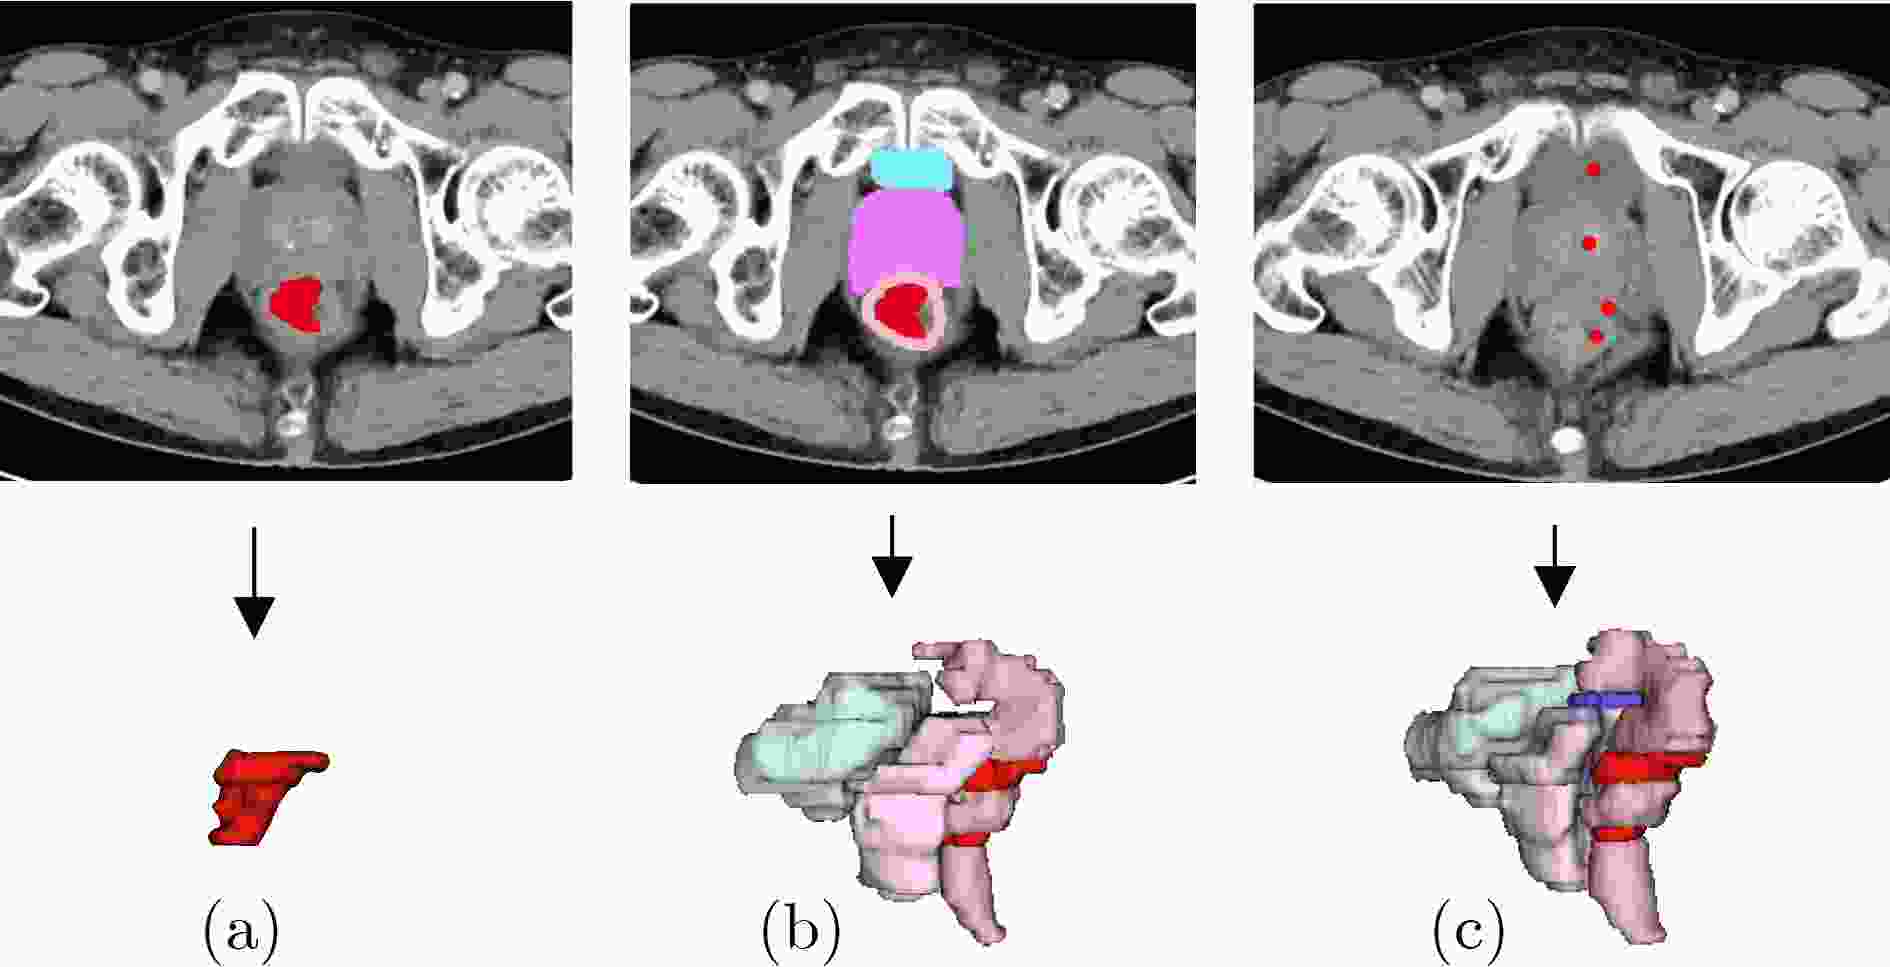

Objective Three-dimensional medical image segmentation is a central task in medical image analysis. Compared with two-dimensional imaging, it captures organ and lesion morphology more completely and provides detailed structural information, supporting early disease screening, personalized surgical planning, and treatment assessment. With advances in artificial intelligence, three-dimensional segmentation is viewed as a key technique for diagnostic support, precision therapy, and intraoperative navigation. However, methods such as SwinUNETR-v2 and UNETR++ depend on extensive voxel-level annotations, which create high annotation costs and restrict clinical use. High-quality segmentation also often requires multi-view projections to recover full volumetric information, increasing radiation exposure and patient burden. Segmentation under sparse radiation measurements is therefore an important challenge. Neural Attenuation Fields (NAF) have recently been introduced for low-dose reconstruction by recovering linear attenuation coefficient fields from sparse views, yet their suitability for three-dimensional segmentation remains insufficiently examined. To address this limitation, a unified framework termed NA-SAM3D is proposed, integrating NAF-based reconstruction with interactive segmentation to enable unsupervised three-dimensional segmentation under sparse-view conditions, reduce annotation dependence, and improve boundary perception. Methods The framework is designed in two stages. In the first stage, sparse-view reconstruction is performed with NAF to generate a continuous three-dimensional attenuation coefficient tensor from sparse X-ray projections. Ray sampling and positional encoding are applied to arbitrary three-dimensional points, and the encoded features are forwarded to a Multi-Layer Perceptron (MLP) to predict linear attenuation coefficients that serve as input for segmentation. In the second stage, interactive segmentation is performed. A three-dimensional image encoder extracts high-dimensional features from the attenuation coefficient tensor, and clinician-provided point prompts specify regions of interest. These prompts are embedded into semantic features by an interactive user module and fused with image features to guide the mask decoder in producing initial masks. Because point prompts provide only local positional cues, boundary ambiguity and mask expansion may occur. To address these issues, a Density-Guided Module (DGM) is introduced at the decoder output stage. NAF-derived attenuation coefficients are transformed into a density-aware attention map, which is fused with the initial masks to strengthen tissue-boundary perception and improve segmentation accuracy in complex anatomical regions. Results and Discussions NA-SAM3D is evaluated on a self-constructed colorectal cancer dataset comprising 299 patient cases (collected in collaboration with Nanjing Hospital of Traditional Chinese Medicine) and on two public benchmarks: the Lung CT Segmentation Challenge (LCTSC) and the Liver Tumor Segmentation Challenge (LiTS). The results show that NA-SAM3D achieves overall better performance than mainstream unsupervised three-dimensional segmentation methods based on full radiation observation (SAM-MED series) and reaches accuracy comparable to, or in some cases higher than, the fully supervised SwinUNETR-v2. Compared with SAM-MED3D, NA-SAM3D increases the Dice on the LCTSC dataset by more than 3%, while HD95 and ASD decrease by 5.29 mm and 1.32 mm, respectively, indicating improved boundary localization and surface consistency. Compared with the sparse-field-based method SA3D, NA-SAM3D achieves higher Dice scores on all three datasets ( Table 1 ). Compared with the fully supervised SwinUNETR-v2, NA-SAM3D reduces HD95 by 1.28 mm, and the average Dice is only 0.3% lower. Compared with SA3D, NA-SAM3D increases the average Dice by about 6.6% and reduces HD95 by about 11 mm, further confirming its capacity to restore structural details and boundary information under sparse-view conditions (Table 2 ). Although the overall performance remains slightly lower than that of the fully supervised UNETR++ model, NA-SAM3D still shows strong competitiveness and good generalization under label-free inference. Qualitative analysis shows that in complex pelvic and intestinal regions, NA-SAM3D produces clearer boundaries and higher contour consistency (Fig. 3 ). On public datasets, segmentation of the lung and liver also shows superior boundary localization and contour integrity (Fig. 4 ). Three-dimensional visualization further confirms that in colorectal, lung, and liver regions, NA-SAM3D achieves stronger structural continuity and boundary preservation than SAM-MED2D and SAM-MED3D (Fig. 5 ). The DGM further enhances boundary sensitivity, increasing Dice and mIoU by 1.20% and 3.31% on the self-constructed dataset, and by 4.49 and 2.39 percentage points on the LiTS dataset (Fig. 6 ).Conclusions An unsupervised three-dimensional medical image segmentation framework, NA-SAM3D, is presented, integrating NAF-based reconstruction with interactive segmentation to achieve high-precision segmentation under sparse radiation measurements. The DGM effectively uses attenuation coefficient priors to enhance boundary recognition in complex lesion regions. Experimental results show that the framework approaches the performance of fully supervised methods under unsupervised inference and yields an average Dice improvement of 2.0%, indicating strong practical value and clinical potential for low-dose imaging and complex anatomical segmentation. Future work will refine the model for additional anatomical regions and assess its practical use in preoperative planning. -